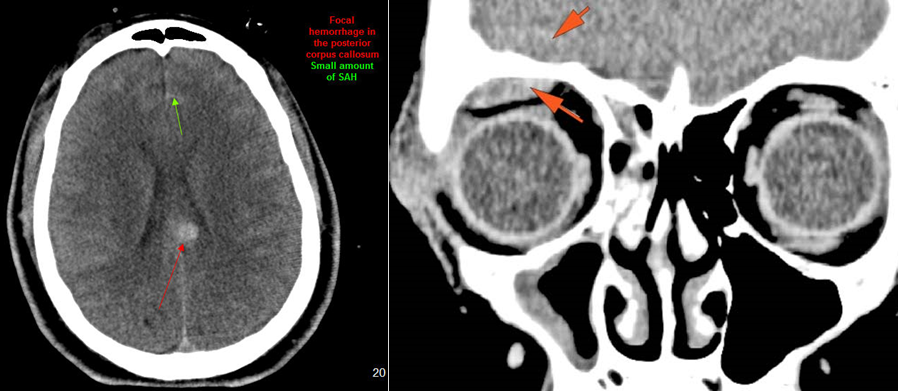

Intracranial and Calvarium

There is evidence of extracranial gas or a foreign body at a possible fracture site.

There is a calvarial fracture.

There is subperiosteal, epidural or subdural hematoma and/or pneumocephalus along the boney walls of the anterior, middle or posterior cranial fossa or elsewhere.